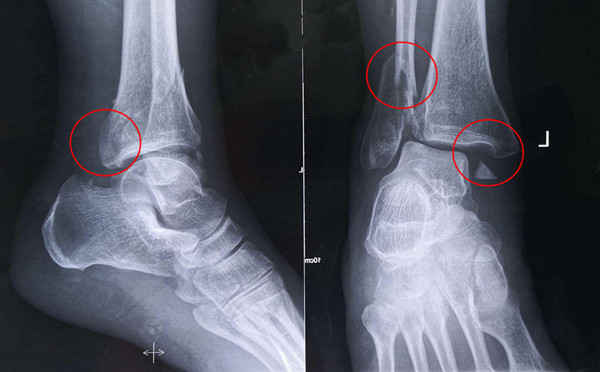

踝關節(jié)骨折在X影像上的表現(xiàn)有很多種。如內(nèi)踝骨折和外踝骨折,我們可以在影像上看到骨折處的骨折線是不連續(xù)的。還有后踝的骨折,內(nèi)踝、外踝、后踝聯(lián)合在一起發(fā)生的骨折,我們稱之為“三踝骨折”,這些都是在X影像上能夠顯示出來的。

內(nèi)踝骨折

有一種特殊類型的踝關節(jié)骨折,可能在X影像平片上就不能顯示出來,它就是脛骨的關節(jié)面往里塌陷,我們又稱之為叫“Pilon骨折”。當它往里塌陷后,我們在X影像平片上可能看不出來它是否塌陷,但是我們在CT上可以360°看到踝關節(jié)的影像,這樣就可以看出患者是否存在踝關節(jié)塌陷的骨折。同樣道理,我們在做Pilon骨折手術的時候,普通二維的X影像并不能判斷我們手術復位情況的好壞,這個時候如果醫(yī)生手上有能夠照三維影像的工具,那么對于醫(yī)生的準確手術是非常有好處的。